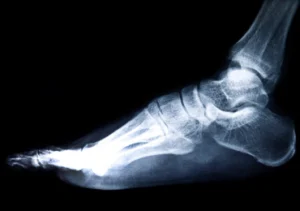

Calcaneal Spur and Plantar Fasciitis A heel spur is a calcium deposit causing a bony protrusion on the underside of the heel bone. On an X-ray, a heel spur can extend forward like a hook. Many calcaneal spurs are asymptomatic and pain usually comes with associated soft tissue inflammation. Heel spurs are your body’s responseRead…